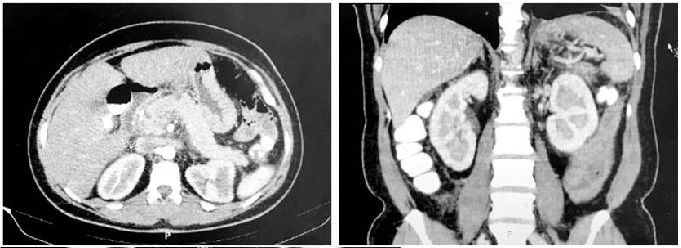

Se realizó una ecografía biliar que descartó colelitiasis y coledocolitiasis, aunque hubo evidencia de inflamación pancreática. Una tomografía axial computarizada (TAC) abdominal contrastada mostró necrosis en el cuerpo del páncreas sin identificar colecciones definidas, compatible con pancreatitis aguda necrotizante (Balthazar C) (Figura 2) y una colangiorresonancia mostró que la paciente tenía pancreatitis aguda edematosa intersticial con una colección peripancreática de 32 x 23 mm (Figura 3), la cual se clasificó como moderada, según el índice de gravedad clínica, con un APACHE II (Acute Physiology and Chronic Health Evaluation II) de 6 puntos, y una valoración de 1 punto en la clasificación modificada de Marshall.

En este caso, el diagnóstico se realizó por exclusión. Se solicitó una ecografía abdominal que descartó etiología biliar; la TAC abdominal contrastada fue la segunda elección, esta mostró la presencia de pancreatitis necrotizante y una posible colección que fue aclarada mediante una colangiorresonancia.

La ecografía hepatobiliar es un método útil para el diagnóstico inicial; sin embargo, presenta una sensibilidad del 25 %-86 % para identificar la AHP y disminuye en cuadros de pancreatitis9. La TAC abdominal contrastada es el estándar de oro imagenológico para determinar el grado de gravedad de la pancreatitis e identificar complicaciones pancreáticas y extrapancreáticas, así como colecciones. La resonancia magnética (RM) es el estudio alternativo en caso de contraindicación o incertidumbre al diagnóstico1.